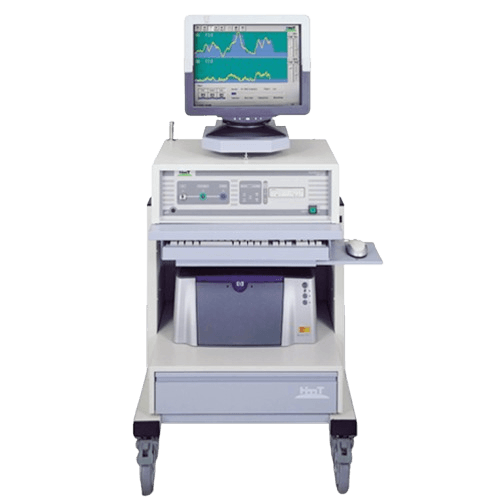

Pelvic Floor Muscle Training (PFMT) Training technique visualizing pelvic floor contraction on screen using biofeedback. Helps learn proper Kegel exercises for managing incontinence and laxity.